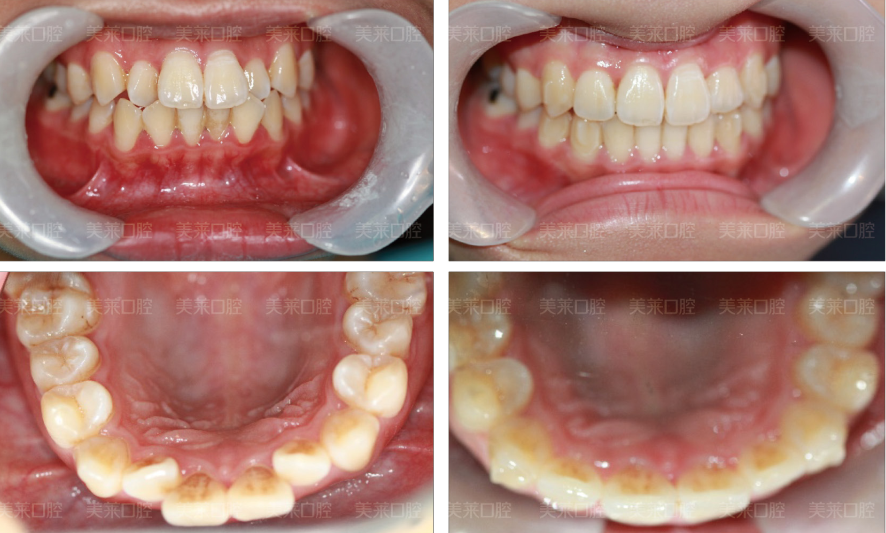

术前症状:牙槽骨突出增生

接受手术:美莱韩式正牙

在往后的日子里,卢小姐失落了好久,越发觉得自己的牙槽骨很凸,看人的样子又有点凶恶的眼神,整个画面显得非常不自然。看着镜子里失落的自己像是突然老了好多,为什么努力了那么久还是被打回“原形”?如此一来,一直用事业伪装自己自卑的她又开始陷入迷茫的漩涡里。后来,卢小姐通过网络各种渠道了解到了深圳美莱口腔的韩式外科正牙术可以快速有效地矫正与牙齿、上下牙槽骨发育有关的畸形和缺陷,特别适合成年人以及口腔矫治器难以纠正的严重牙列和颌面畸形。再把网上的相关案例跟自己的龅牙症状对照了一下才下决心想整牙。>> 点击在线咨询了解更多牙齿问题

其实,卢小姐的五官长得还是很不错的,就是因为牙槽骨突出扭曲了整体上的美感,现在卢小姐已经做完手术了,当我们看到做完手术的她样子跟变了魔术似的,鹅蛋脸是每一个爱美人士都想拥有的,而卢小姐很成功的拥有了。通过美莱韩式正牙,只是1小时的手术时间,便看到了预期中的改造效果;消肿恢复之后,面容形态完全显露,美观协调的容貌让她的整体气质也上了一个层次,标准的笑容给她的形象加分,眼睛里时刻都闪耀自信的光芒,希望在以后的日子里卢小姐的生活、工作能够愈加如鱼得水。